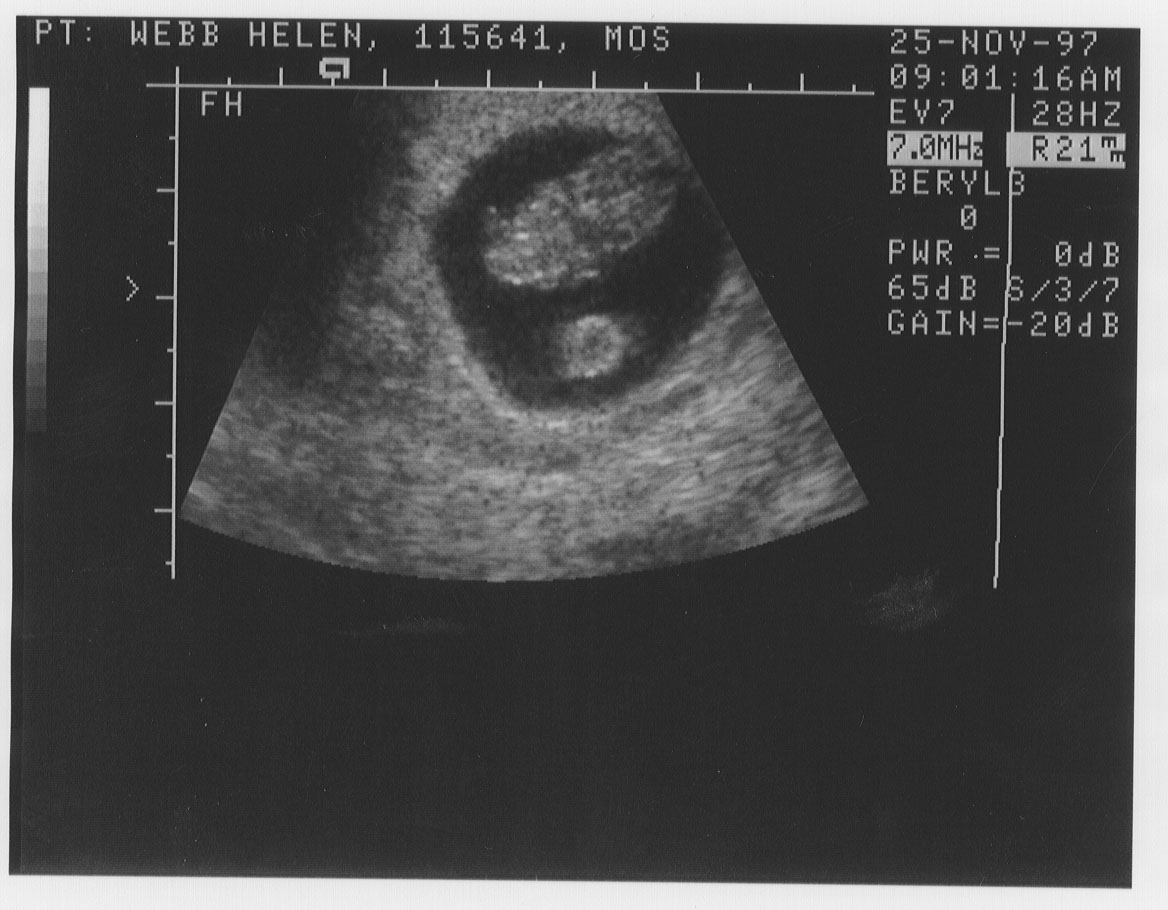

It's never too early to start embarrassing your kid (or kid-to-be). So here are the first baby pics. Years from now, you can say "I remember when you were just 1.9cm long...."

9 weeks, about 1.9cm.